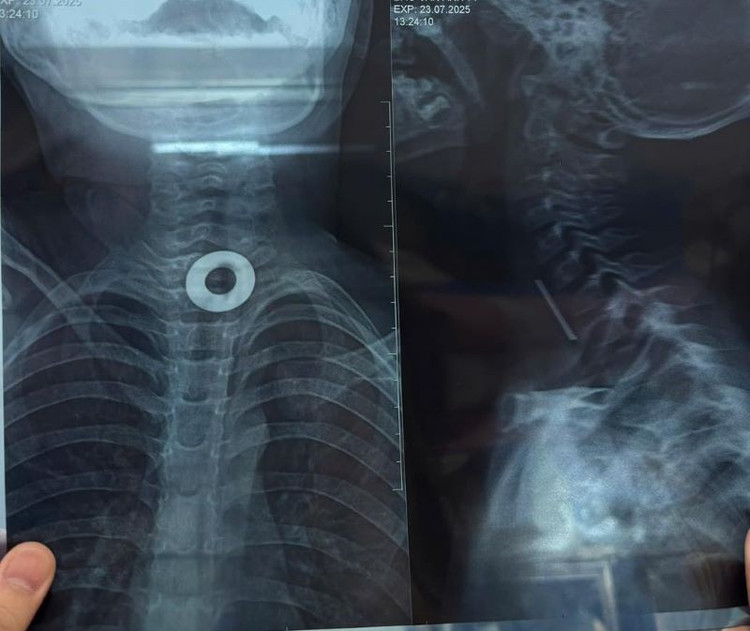

Ngày 24/7, Các bác sĩ khoa Thăm dò chức năng, Bệnh viện Đa khoa Hà Nam đã gắp thành công một miếng kim loại hình tròn (long đen) từ trong thực quản cháu bé 7 tuổi ra ngoài.

Dị vật trong thực quản trẻ trên phim chụp - Ảnh BVCC

Sau khi vào viện, cháu bé được thăm khám và nội soi. Kết quả cho thấy có một dị vật kim loại hình tròn đường kính khoảng 2cm kẹt ở thực quản đoạn 1/3 trên thực quản.